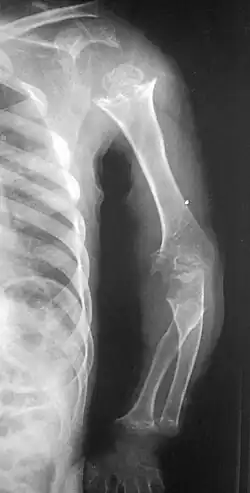

Pseudoachondroplasia. Shoulder and humerus. Note the dysplastic proximal humeral epiphysis, metaphyseal broadening, irregularity and metaphyseal line of ossification. These changes are collectively known as "rachitic-like changes". Lesions are bilateral and symmetrical.

• Together with rhizomelic limb shortening, the presence of epiphyseal-metaphyseal changes of the long bones is a distinctive radiologic feature of pseudoachondroplasia.

• Dysplastic/hypoplastic epiphyses especially of shoulders and around the knees.

• Metaphyseal broadening, irregularity and metaphyseal line of ossification. These abnormalities that are typically encountered in proximal humerus and around the knees are collectively known as "rachitic-like changes".

• Radiographic lesions of the appendicular skeleton are typically bilateral and symmetric.